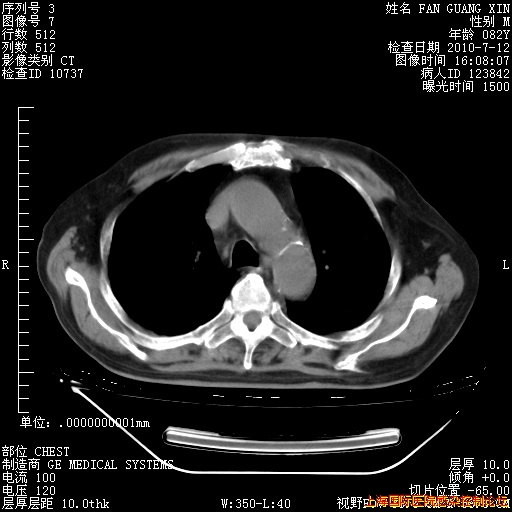

6月12日纵膈窗

今天CT

整整相隔30天的肺部CT好像有所好转啊。甲强龙减量第3天,需要观察体温。